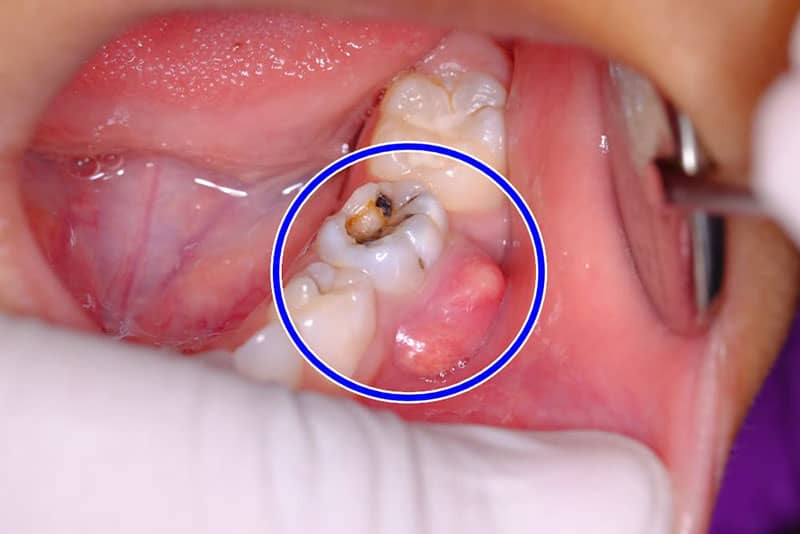

• باقی ماندن یک کانال ریشه

تعداد کانال های ریشه در دندان های مختلف و همچنین افراد گوناگون، متفاوت است. همین موضوع سبب می شود به دلیل پیچیدگی بعضی کانال ها و عدم مشاهده یک یا چند مورد از آنها، درمان عصب کشی کامل صورت نگیرد. باقی ماندن یک یا چند کانال ریشه که عصب کشی نشده باشند و پالپ عفونی از آنها خارج نشده باشد بعد از درمان نیز با خود درد به همراه دارند. برای برطرف کردن درد نیاز به انجام عصب کشی مجدد می باشد.